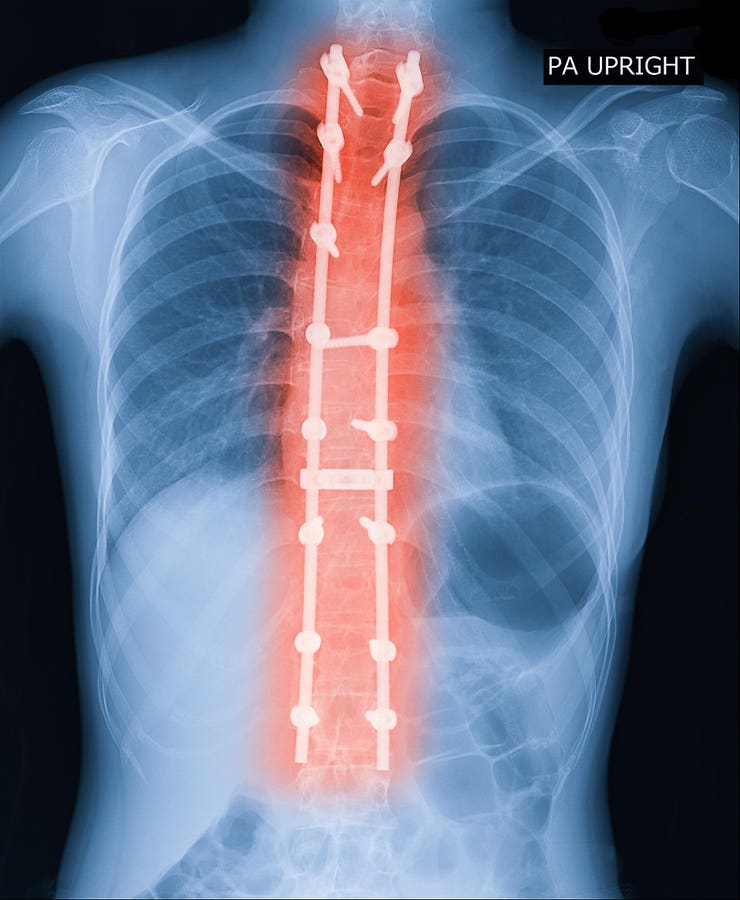

New Groundbreaking Scoliosis Study 8 Years In The Making: What To Know